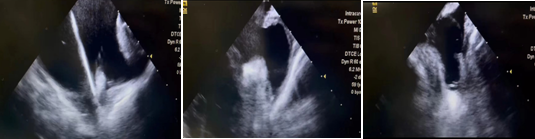

此例手术由韩稳琦博士和酉鹏华博士通过ICE指导下进行,通过ICE精准构建心脏模型、直视下穿刺房间隔,结合三维标测系统,精准、高效地完成双侧肺静脉隔离。后通过ICE及左心耳造影评估左心耳特征为下缘短,上缘折角大的短颈鸡翅型心耳,利用12F导引系统鞘管和猪尾导管在DSA肝位下同时造影,测量左心耳开口25.12mm,最大可用锚定区深度19.71mm,最终选择31mm规格watchman FLX封堵器的植入。ICE从不同角度检查即将释放的WATCHMAN FLX左心耳封堵器,观察封堵器位置、露肩、残余分流和压缩比情况,明确封堵器位置合理,无明显露肩,完全封堵无残余分流,封堵器位置良好。随后在ICE下观察及DSA透视下作牵拉试验,直到最后一次牵拉与前一次牵拉比较无位置改变,压缩比无明显变化,符合封堵器释放的“PASS”原则后完全释放封堵器。

图1 ICE观察测量左心耳开口及深度